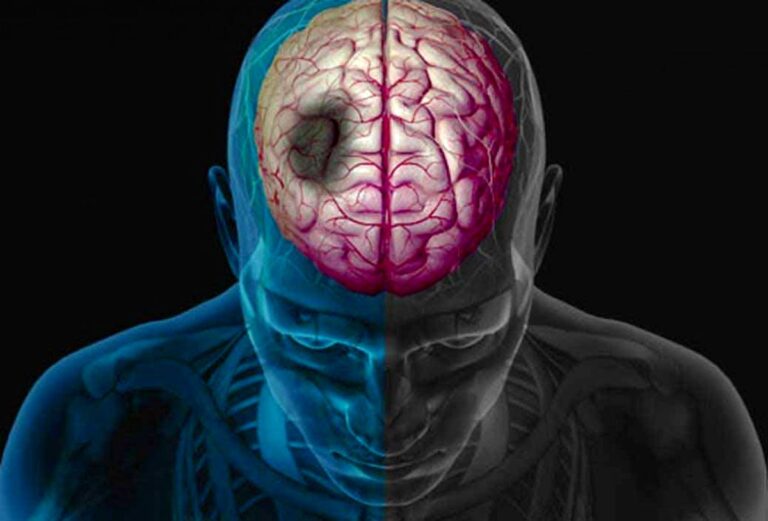

آنوریسم مغزی برآمدگی در یک رگ خونی در مغز است که میتواند باعث خونریزی مغزی در نتیجه نشت یا پارگی شود. این وضعیت نیاز به مراقبت فوری پزشکی دارد زیرا زندگی بیمار را تهدید میکند. آیا آنوریسم مغزی باعث مرگ میشود؟ پارگی آنوریسم سریعاً تهدیدکننده زندگی است و نیاز...

ورم مغزی یک آسیب شناسی جدی است که با تجمع غیرطبیعی مایعات داخل سلولی و خارج سلولی در سیستم عصبی مرکزی مشخص میشود و پیامد خطرناک آن افزایش حجم مغز و فشار داخل جمجمه (فشار موجود در سطح جمجمه) است. احتمالا ذهن شما هم درگیر این سوال شده است...

سکته مغزی معمولاً به عنوان یک رویداد تلخ شناخته میشود. سکته مغزی نیز میتواند بدون علائم باقی بماند. در این حالت به آن سکته مغزی خاموش میگویند. در ادامه به بررسی سکته مغزی خاموش، علائم و درمان آن میپردازیم. خطر سکته مغزی خاموش با این حال، هر سکته مغزی...